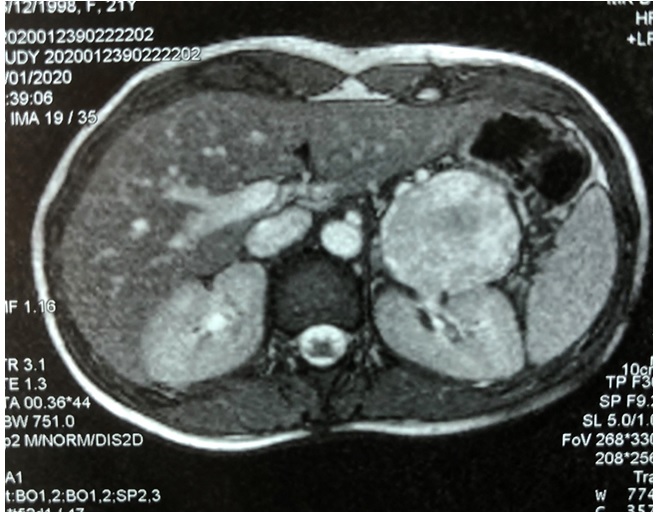

En la tomografía axial computarizada (TC), se evidencia tumoración sólido quística de 70 x 58 x 55 mm, con compresión gástrica. Desplaza arteria y vena esplénica. (Fig. 1)

Fig. 1:  Estudio TC muestra tumoración solido quística de cola de páncreas de 70x58x55mm que comprime estómago, sin infiltración. Arteria y vena esplénica permeables. Wirsung 6-8 mm. Resto del páncreas: normal.

La sintomatología es tardía, por efecto de masa del tumor y crecimiento expansivo; el dolor que se constata entre el 19 % y 87 % de los casos. 6 El estudio imagenológico mediante tomografía computarizada (TC) tiene una sensibilidad del 60 % y muestra un tumor voluminoso, circunscripto con cápsula periférica bien delimitada del páncreas normal (Fig. 1) y calcificaciones en un 30 % de los casos. Estos tumores típicamente se observan como lesiones de densidad mixta, sólidas en la periferia y quísticas en el centro. Pueden existir áreas de hemorragia, como zonas de alta densidad entre la región quística y solida de la lesión. Son tumores que generalmente desplazan estructuras adyacentes más que las7)(8. La resonancia nuclear magnética (RNM) es más eficiente que la TC para detectar los cambios degenerativos como la hemorragia, cambios quísticos y la integridad de la cápsula8.